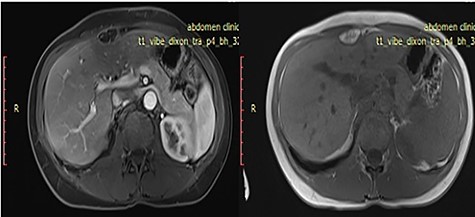

Computed tomography (CT) scan showed a 28 × 13mm solitary mass of fat density, in contact with anterior IV liver segment. Further evaluation with magnetic resonance imaging (MRI) demonstrate an extrahepatic fatty lesion in the anterior perihepatic space adjacent to the falciform ligament (Fig. 1).

Axial T1 weighted images pre- and post-IV contrast sequences demonstrate extrahepatic fatty lesion in the anterior perihepatic space adjacent to the falciform ligament.